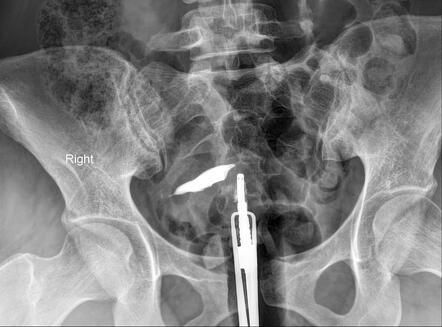

HSG – HysterosalpingoGraphy

During the HSG procedure, the patient lies on an X-ray table, and a speculum is inserted into the vagina to visualize the cervix. The cervix is then cleaned, and a thin catheter is gently inserted through the cervical canal into the uterine cavity. A contrast dye is slowly injected through the catheter, filling the uterine cavity and fallopian tubes. As the dye moves through these structures, a series of X-ray images are taken to capture its flow. This process allows the radiologist to observe the shape and condition of the uterus and the openness of the fallopian tubes in real time.

The results of an HSG can reveal various conditions that affect fertility. Normal results show a uniformly shaped uterine cavity and free passage of dye through open fallopian tubes, indicating no blockages. Abnormal findings may include uterine anomalies like a septate or bicornuate uterus, polyps, fibroids, or scarring (Asherman's syndrome). Tubal blockages, often caused by pelvic inflammatory disease (PID), endometriosis, or previous surgeries, can also be identified. The identification of such abnormalities helps guide further diagnostic and therapeutic steps, improving the chances of successful conception.